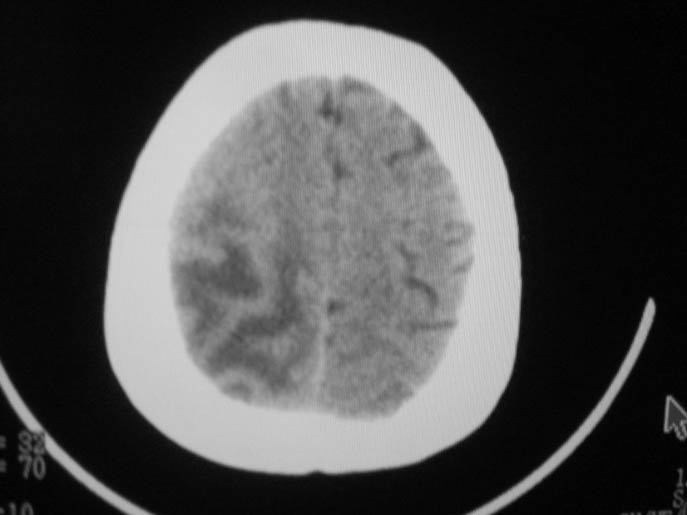

以下是引用卜一在2009-9-7 16:23:00的发言:[br]支持:胶质瘤伴出血!

以下是引用随光逐影在2009-9-8 7:40:00的发言:[br]考虑脑转移瘤或胶质瘤并肿瘤卒中;建议行ct增强扫描检查。

以下是引用熊熊在2009-9-7 18:31:00的发言:[br]胶质瘤伴出血[br]建议增强